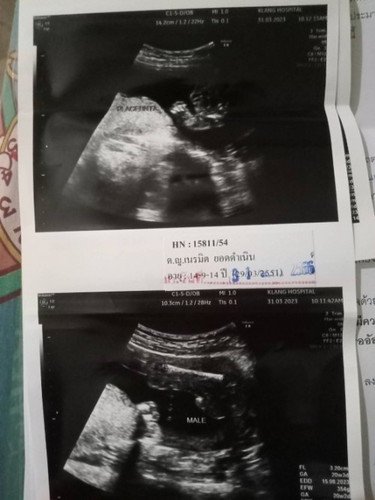

ช่วยดูให้หน่อยครับว่าผู้ชายจริงไหมมองไม่ออกเลยครับใครมีประสบการณ์ช่วยบอกหน่อยว่าตรงไหนคือตัวคือหัว❤️🙏

Male = ผู้ชายค่ะ เห็นเป็นแท่งๆอยู่นะคะคุณพ่อ ยินดีด้วยค่ะ

น่าจะผู้ชายนะคะ เหมือนจู๋น้องโผล่